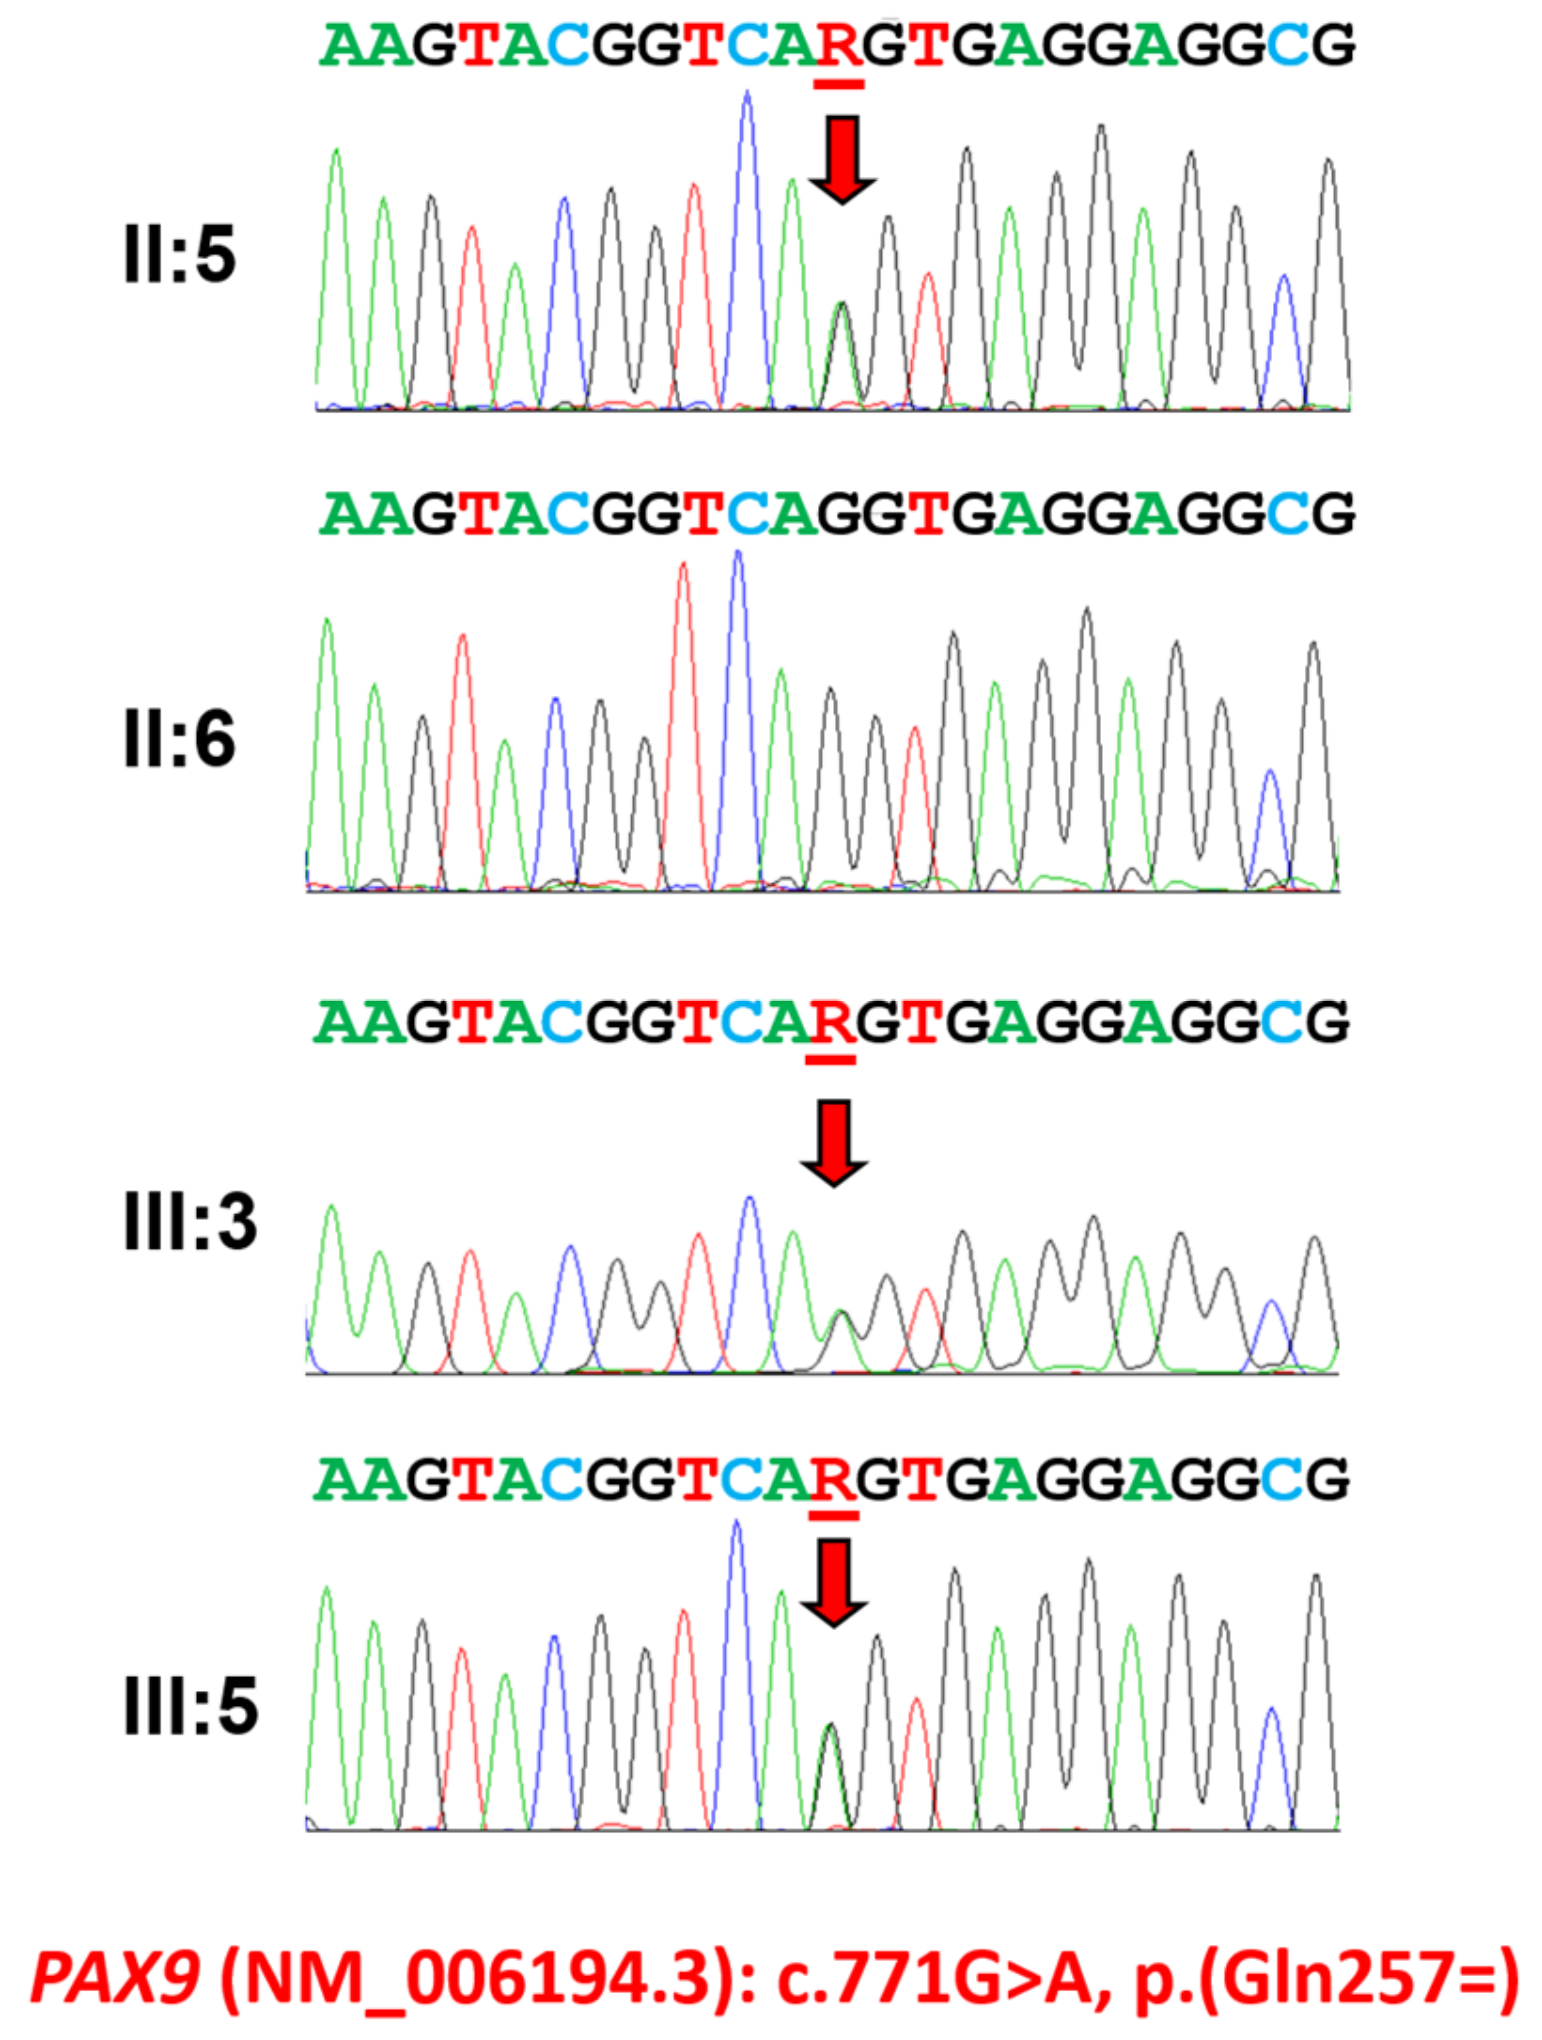

3.1. Family 1